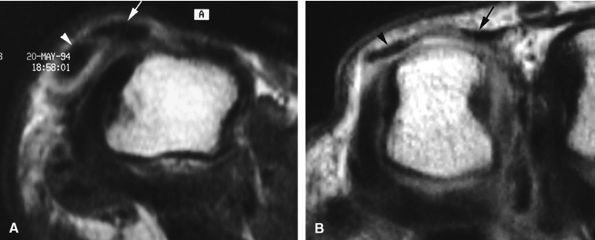

The UCL lies deep to the overlying low-signal adductor aponeurosis on coronal images (Figs. 11.7 and Fig. 11.8). In a nondisplaced partial or complete tear of the UCL, the ligament appears thickened all along its course, sometimes with a small gap. When displaced, the UCL appears as a proximally retracted round or stump-like structure, which demonstrates low signal on all sequences. It is no longer parallel to the long axis of the thumb and presents an increased horizontal orientation.

-

Stener's lesion may present with a “yo-yo on a string” pattern, with the retracted and balled-up UCL representing the yo-yo and the more distal linear adductor aponeurosis representing the string (Fig. 11.9).

On axial images, the ligament may be seen lying above or intersecting the adductor aponeurosis.

FIGURE 11.7 ● Coronal post-contrast T1-weighted image showing a nondisplaced tear of the UCL of the first metacarpophalangeal joint (MP) joint. The torn UCL is elongated beneath the adductor aponeurosis (AA). There is focal enhancement of the tear (asterisk). 1 MC, first metacarpal.

FIGURE 11.8 ● MR arthrography of nondisplaced tear of the UCL of the first MP joint. Coronal (A) and sagittal multiplanar reformatted (MPR) (B) T1-weighted fat-suppressed 3D gradient-echo images showing an oblique tear (asterisk) of the UCL without avulsion. Thearrows mark the distal (black) and proximal (white) aspects of the torn UCL. The sagittal MPR slice is defined along the course of the UCL. MC, metacarpal; AA, adductor aponeurosis.